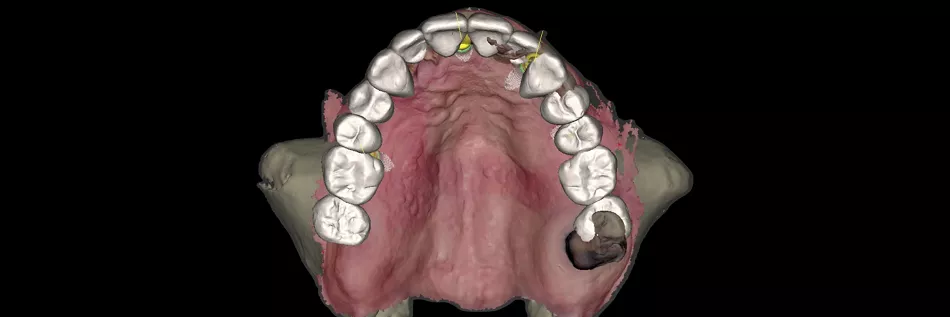

• Segmentation of the bone using AI and superimposition of the intraoral scan file (Fig. 12).

Fig. 12

• Positioning of implants and Novaloc® abutments (Fig. 13).

Fig. 13